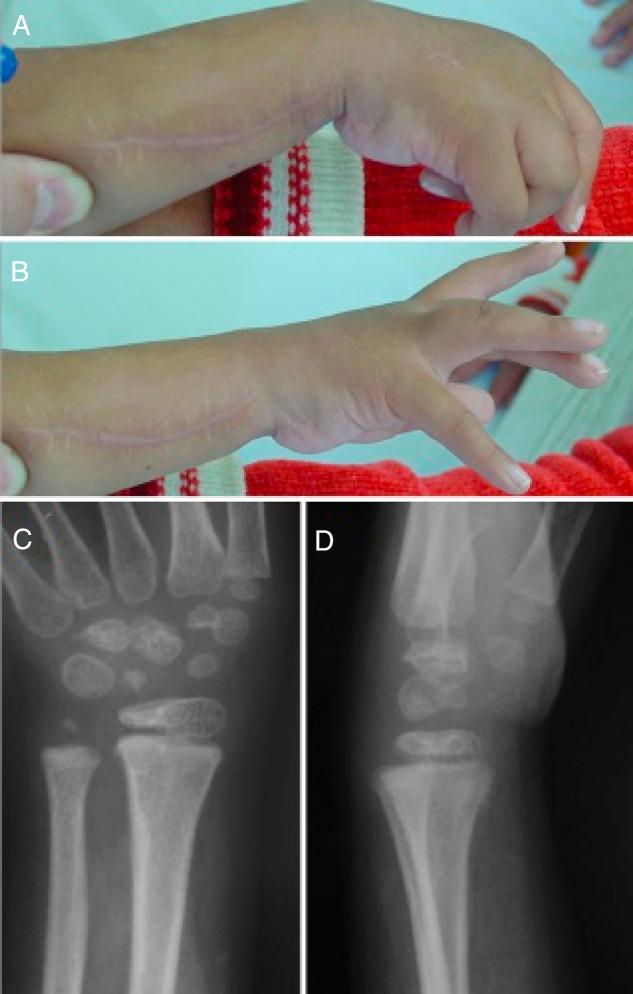

This study analyzed nine patients through a retrospective evaluation with severe deformity in flexion and ulnar deviation of the wrist in the period between January 2004 and December 2009. They were submitted to carpal osteotomy with a biplanar dorsal resection wedge, with a minimum evaluation of 48 months of postoperative evolution. In three patients the osteotomy was bilateral, totalling 12 cuffs analyzed. The indication for the technique described was deformity and stiffness for over six months, without improvement with the conservative treatment.

The mean age of the patients on the day of surgery was five years and eight months. The initial mean wrist mobility was 35°, and the joints presented a mean flexion of 72.5° in a resting position. Osteotomy union occurred in all patients at an average period of 5.7 weeks. The final position of the resting wrist was 12° of flexion and the mean mobility was 26.6°, slightly lower than preoperatively but in a much better position. No serious complications arising from surgery or in the immediate postoperative period were observed.